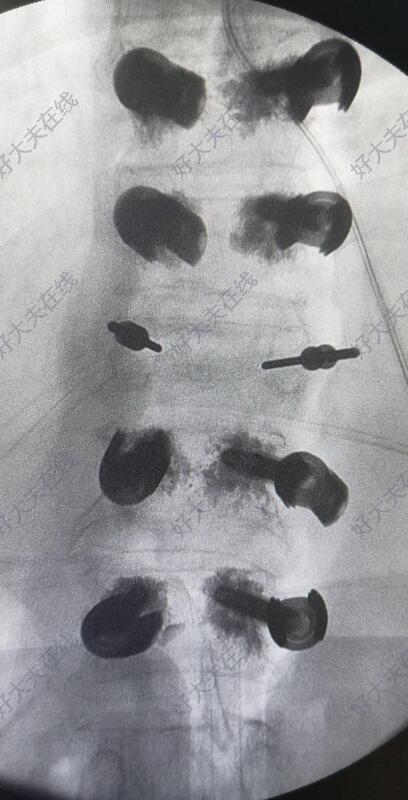

术中于胸10,胸11,腰1,腰2椎体置入骨水泥椎弓根螺钉。透视见骨折复位后,于胸12双侧椎弓根对胸12椎体植骨。